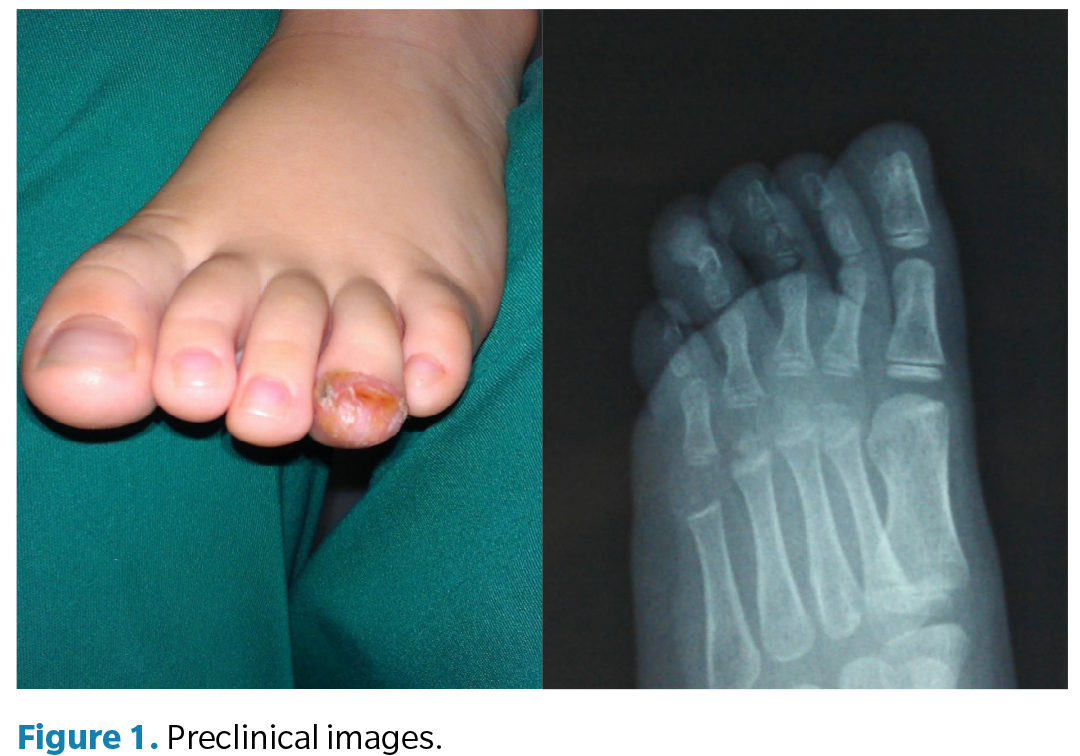

On clinical examination, the patient was in good general condition, with no motor dysfunction in the lower limbs. A distal tumoral lesion was observed on the 4th toe of the left foot, compromising the fingertip and producing nail dystrophy due to elevation of the nail plate (Figure 1). The lesion had well-demarcated borders, erythematous skin on its surface, and a small ulcerated area covered by a crust. Pain was elicited on palpation.

Plain radiography (anteroposterior and oblique views) showed a well-demarcated, bone-dense image originating in continuity with the distal phalanx of the 4th toe, consistent with the diagnosis of subungual osteochondroma.